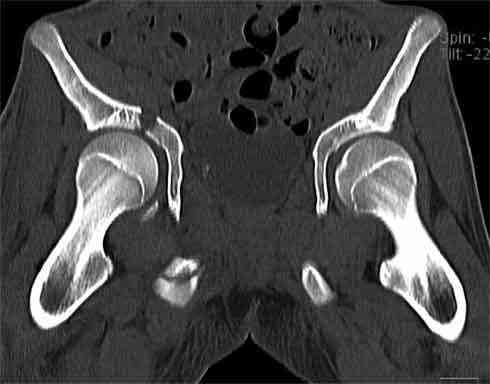

Не смог разглядеть на представленных картинках частичное повреждение левого КП, повреждение Денис1-2 справа? 3Д реконструкции в инлет и боковой проекциях убедительно не демонстрируют типа повреждения задних отделов тазового кольца(справа боковая масса скомпремирована), Наверное, у тебя есть возможность оценить тип перелома крестца по прямой проекции 3Д.

Думаю, что КТ заднего отдела показала бы ясно тип повреждения .

В данном случае 3D и корональные срезы КТ менее информативны, чем поперечные. Согласен с левосторенним минимальным повреждением КПС, но не смог уловить перелом крестца.

На 3D по линии перелома ацетабулум возможно сверху в подздошной кости уже есть сращение? или состояние перелома у молодых, после неполного (при пластической деформации) перелома.

По представленным материалам, мне кажется, перелом был передней колонны ацетабулум с минимальным вовлечением нагрузочной поверхности сустава, левосторенний повреждение КПС и лонных костей.

При свежем случае показана фиксация передней колонны к задней (снимки), компрессирующим винтом минимальным перкутанным методом по супраацетабулярной линии и в зависимости от состояния КПС.